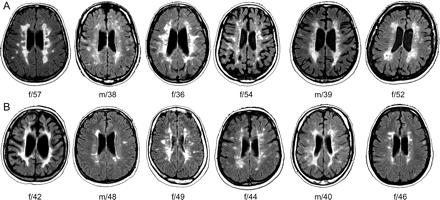

Multiple sclerosis- paraventricular white matter lesions

-multiple, bilateral, asymmetric hyperintense lesions representing clusters of demyelinated neurons